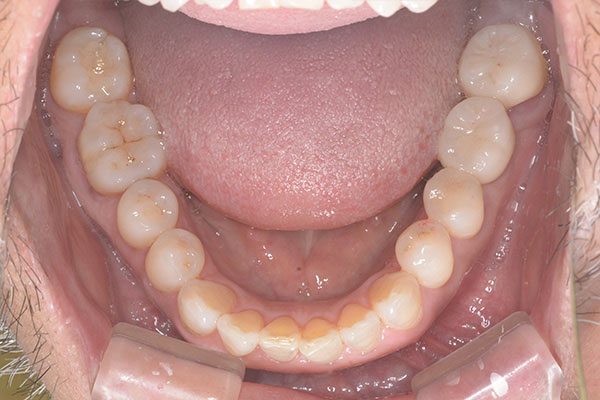

Case.03

インプラントの症例 インプラントの症例

治療前〜治療後のレントゲン写真

患者様の要望過去に治療したブリッジを外し咬み合わせの平面を整えて、被せ物や詰め物を綺麗にしたい。

治療期間10ヶ月

治療費用1,600,000円

治療内容インプラント2本、アンカースクリューを用いた部分矯正、

セラミックによる補綴治療

治療のリスクセラミックの破折の可能性